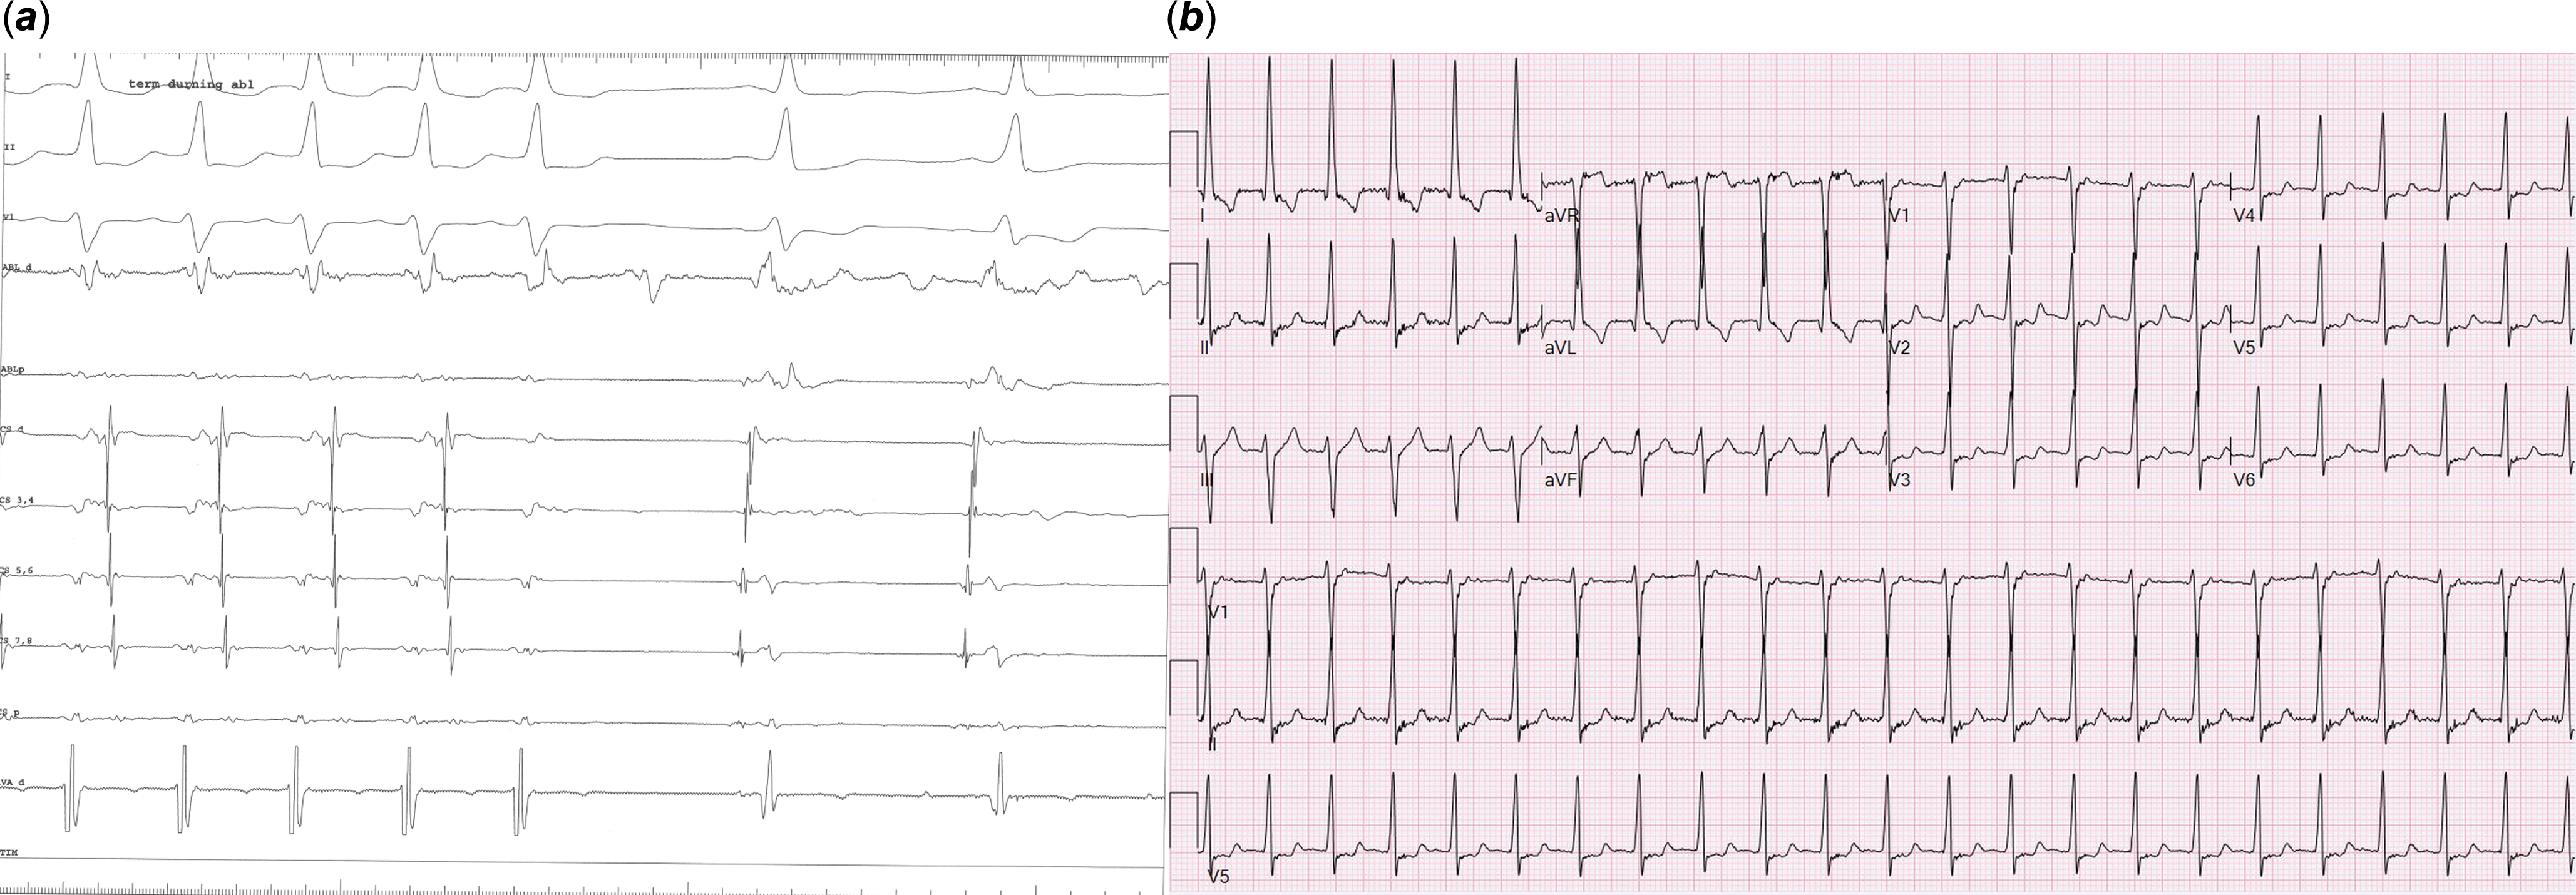

A 17-year-old girl presented with palpitations and Wolff–Parkinson–White pattern on electrocardiogram (Figure 1). Her echocardiogram was suggestive of left ventricular non-compaction with preserved ejection fraction (Figure 2A, Video 1). This was confirmed on cardiac magnetic resonance imaging per criteria proposed by Petersen et al (Figure 2B, Video 2).Reference Petersen, Selvanayagam and Wiesmann7 She underwent an exercise stress test during which pre-excitation persisted at a peak heart rate of 171 beats per minute suggesting a possible high-risk pathway. She subsequently underwent an electrophysiology study during which orthodromic reentrant tachycardia was induced (cycle length of 460 msec) with programmed atrial stimulation. On decremental atrial pacing, the accessory pathway block cycle length was < 200 milliseconds and the shortest preexcited RR interval during atrial fibrillation measured 174 msec (Figure 3), findings which confirmed the pathway to be high risk. The episode of atrial fibrillation resulted in haemodynamic instability and required immediate cardioversion. Mapping was therefore only performed during pre-excited sinus rhythm. Earliest ventricular activation during sinus rhythm was noted over a broad area in mid coronary sinus and superolateral mitral annulus. However, application of radiofrequency energy at these sites was not successful in eliminating pre-excitation (Figure 4). She was started on sotalol until she underwent another EP study a month later. This time, the earliest ventricular activation during sinus rhythm was recorded over a broad area located from 2 to 4 o’clock along the mitral valve annulus. Empiric radiofrequency ablation was performed at the site. Orthodromic reentrant tachycardia was induced following initial ablations (Figure 5A), but no tachycardia could be induced following consolidation of the site. No ventriculoatrial conduction was noted following consolidation. Anterograde accessory pathway conduction, however, persisted, but antegrade pathway block occurred at an atrial pacing cycle length of 450 msec suggesting that the pathway had been modified. Eighteen months following the second ablation, the patient presented to the emergency department in supraventricular tachycardia, which was terminated with adenosine (Figure 5B). She is currently treated with flecainide 75 mg twice daily and is doing well.

Figure 4. Broad area of RF ablation along the lateral mitral annulus (Panel A) and coronary sinus (Panel B) failed to eliminate pre-excitation.

Figure 5. Panel a shows loss of retrograde pathway conduction with RF ablation during the second EP study. Panel B shows narrow QRS SVT (orthodromic reentrant tachycardia) 18 months after second ablation which required adenosine for termination.